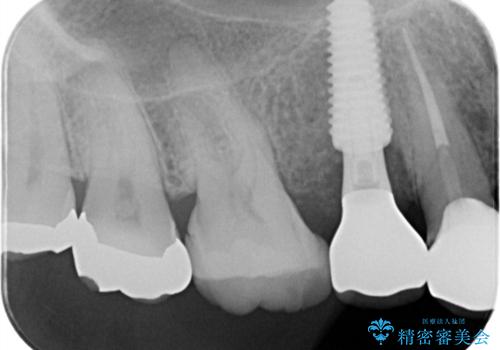

- 右上の歯に異和感があるとの事で来院した患者様です。

検査の結果、歯根破折が認められたため、抜歯即時インプラント(1DAYインプラント)を行いました。

1日で抜歯、インプラント埋入、骨補填材を填入し仮歯【1DAYインプラント】までを数時間で行いました。